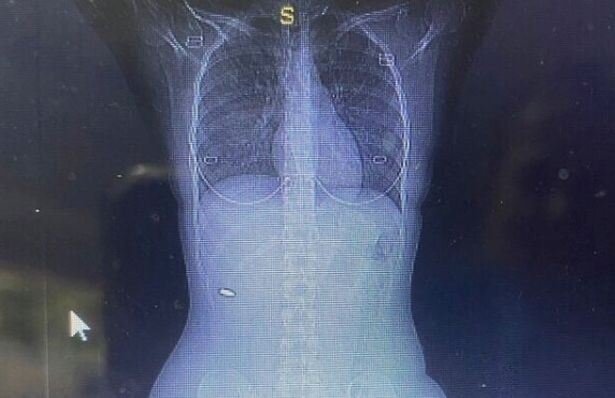

Молодая женщина через три месяца после странного происшествия поняла, что в нее стреляли на свадьбе на Западном берегу недалеко от Палестины. Она сделала компьютерную томографию и обнаружила рядом с позвоночником пулю. Об этом сообщило Times of Israel.

Однако боль не проходила, и Ади попросила сделать компьютерную томографию. Сканирование обнаружило кусок металла возле ее позвоночника, и только после операции врачи поняли, что это пуля калибра 5,56 мм.

Блой сказала: «Я была спасена чудом. Врач-хирург сказал мне, что если бы пуля попала на несколько сантиметров в сторону (в любом направлении), то мне бы это причинило много вреда».